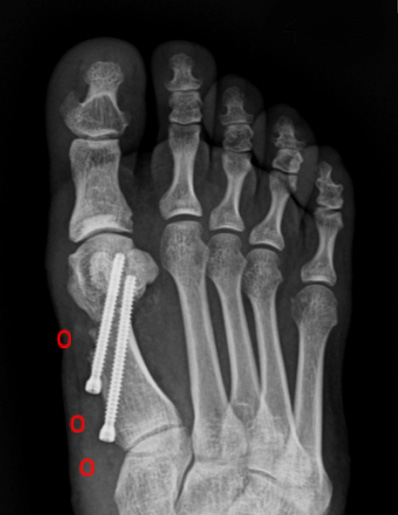

수술 전

수술 후

작은 구멍을 통해 초음파 절골기를 이용하여 뼈를 절골합니다.

4세대 MICA 방법을 이용하면 개방적 방법만큼의 각 교정도 가능하기 때문에

중등도 이상의 큰 각도의 무지외반증에도 충분히 적용이 가능합니다.